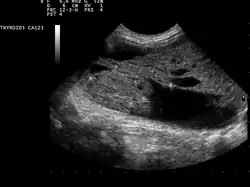

Ultrasound artifacts showing a "comet tail" from a colloid nodule indicate a benign nodule

Ultrasound imaging is useful as the first-line, non-invasive investigation in determining the size, texture, position, and vascularity of a nodule, accessing lymph nodes metastasis in the neck, and for guiding fine needle aspiration cytology (FNAC) or biopsy. Ultrasonographic findings will also guide the indication to biopsy and the long term follow-up.[10] High frequency transducer (7–12 MHz) is used to scan the thyroid nodule, while taking cross-sectional and longitudinal sections during scan. Suspicious findings in a nodule are hypoechoic, ill-defined margins, absence of peripheral halo or irregular margin, fine, punctate microcalcifications, presence of solid nodule, high levels of irregular blood flow within the nodule[11] or "taller-than-wide sign" (anterior-posterior diameter is greater than transverse diameter of a nodule). Features of benign lesion are: hyperechoic, having coarse, dysmorphic or curvilinear calcifications, comet tail artifact (reflection of a highly calcified object), absence of blood flow in the nodule, and presence of cystic (fluid-filled) nodule. However, the presence of solitary or multiple nodules is not a good predictor of malignancy. Malignancy is only diagnosed when ultrasound findings and FNAC report are suggestive of malignancy.[11] The TI-RADS (Thyroid Imaging Reporting and Data Systems) are sonographic classification systems which describe the suspicious findings of thyroid nodules.[12] It was first proposed by Horvath et al.,[13] based on the BI-RADS (Breast Imaging Reporting and Data System) concept. Several systems were subsequently proposed and adopted by international scientific societies. Their main aims are to characterize the risk of malignancy of nodules to better select nodules to submit to fine-needle aspiration cytology.[14] TI-RADS developed by the American College of Radiology (ACR) guides clinicians in deciding which nodules require FNAC and in planning follow-up. Various online tools have been developed to assist in applying these criteria to clinical practice. [15]